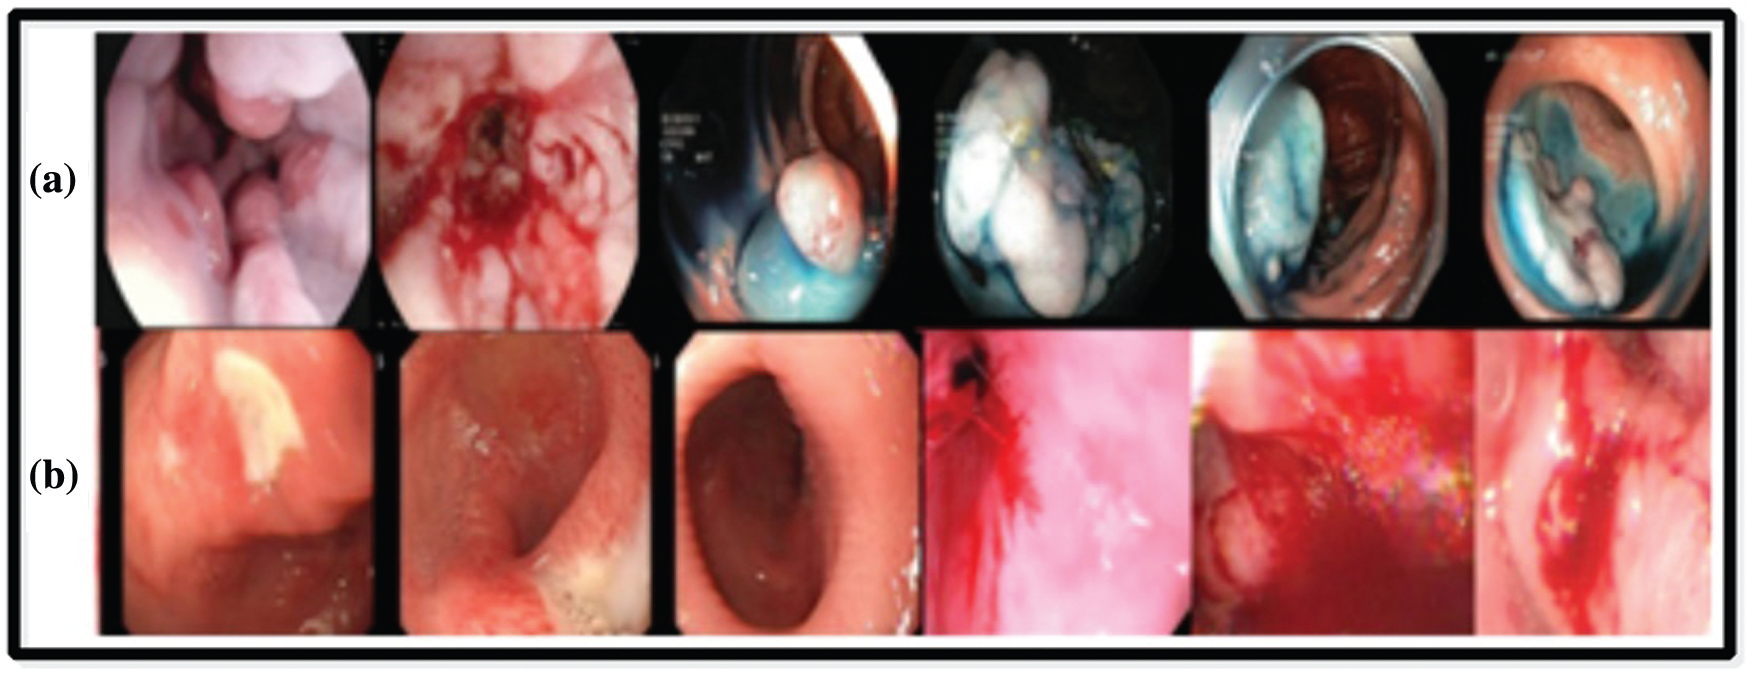

KVASIR Dataset contains a total of 4000 images, which are confirmed by expert doctors [36]. Eight different types of infections are included in this dataset, such as Dyed-Lifted-Polyp (DLP), Dyed-Resection-Margin (DRM), Esophagitis (ESO), Normal-Cecum (NC), Normal-Pylorus (NP), Normal Z-Line (NZL), Polyps (P), and Ulcerative-Colities (UCE). Every class contains 500 images of different resolution-

Private Dataset was collected from COMSATS Computer Vision Lab [37], and it includes a total of 2326 clinical sample images. These images consist of three categories-ulcer, bleeding, and healthy. The image size is

Figure 8: Sample images selected from the datasets: (a) KVASIR dataset [36], (b) Private dataset [37]